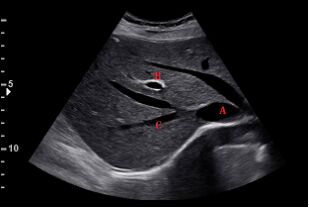

66.下圖為肋骨弓下緣之超音波掃描影像,其編號A、B、C的解剖位置,依序應為下列何者? (A)腹主動脈、門靜脈、左肝靜脈(B)腹主動脈、肝動脈、右肝靜脈(C)下腔靜脈、門靜脈、右肝靜脈(D)下腔靜脈、門靜脈、左肝靜脈